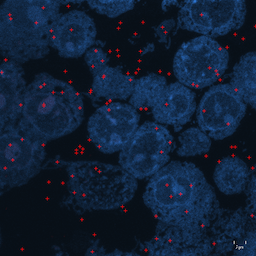

For image analogies based image registration, I have corresponding TEM/Confocal Microscopic image pairs of mouse brains with corresponding regions highlighted by a box. Using the correlative microscopy technique on the mouse brain, I want to localize specific brain regions associated with Pelizaeus-Merzbacher Disease (PMD) and do quantitative assessment of hypomyelination and demyelination in mice. PMD is one of a group of genetic disorders characterized by progressive degeneration of the white matter of the brain affecting the myelin sheath, the fatty covering that acts as an insulator on nerve fibers in the central nervous system.

The confocal microscopy images are multichannel color images in our test dataset. The blue channel is based on the blue stain DAPI (a fluorescent stain) which stains the DNA of the cell nucleus and corresponds to dark regions within the nuclei in the TEM. The green channel is based on the stains of the myelin sheats, visible as dark black layers covering the neurons in the TEM images. The red channel is not explicitly stained for and is caused by the auto-fluorescent effect of lipofuscin. The confocal image with RGB channels and its corresponding TEM image are shown in Fig. 5.

Currently I have six pairs of 2D TEM/confocal images with resolutions 582.24 pixels per μm𝜇𝑚\mu m and 7.5887.5887.588 pixels per μm𝜇𝑚\mu m respectively (1μm=1micron=106m1𝜇𝑚1𝑚𝑖𝑐𝑟𝑜𝑛superscript106𝑚1\,\mu m=1\,micron=10^{-6}\,m). The resolution is different between two images and only a small region in the confocal image corresponds to the TEM image.

From the example in Fig. 5, the blue and red channels are too noisy and contain less information compared to the green channel. We use only the green channel as grayscale image for the registration in our application. The datasets are roughly registered based on manually labeled landmarks with a similarity transformation model.

Refer to caption

(a) Red channel of confocal image

(b) Green channel of confocal image

(c) Blue channel of confocal image

(d) Grayscale of confocal image

(e) Confocal image

(f) TEM image

Figure 5: Example of Confocal image with RGB channels and TEM image